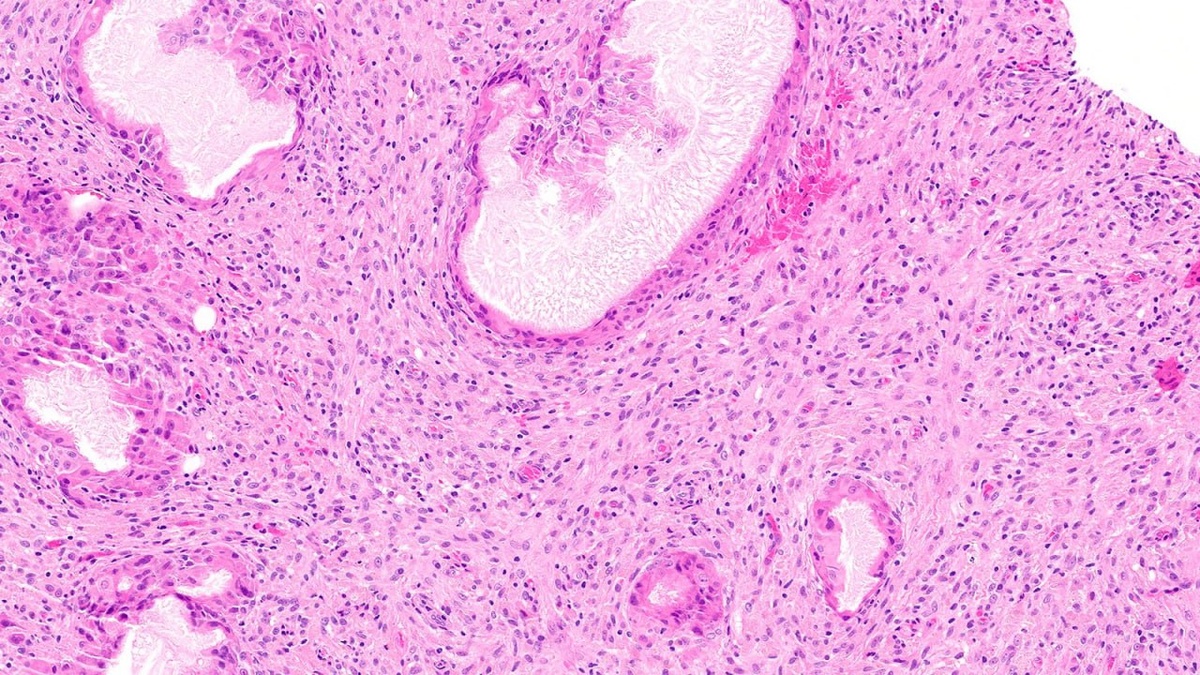

Случай веретеноклеточной гистиоцитарной псевдоопухоли молочной железы 🔬 Реактивное веретеноклеточное образование из гистиоцитов, вероятно, являющееся выраженной формой жирового некроза. Название этого образования длиннее самого процесса, но оно точно отражает его природу. #молочнаяжелеза #гистология #псевдоопухоль

Реактивное веретеноклеточное образование из гистиоцитов, вероятно, являющееся выраженной формой жирового некроза. Название этого образования длиннее самого процесса, но оно точно отражает его природу.